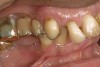

A patient with Stage 1 demineralization (Figure 2) presents with exposed root surfaces that appear dull when dried and illuminated. When palpated with the side of the explorer, the root surface feels rough and slightly soft to pressure from the side of the explorer. Color changes associated with D1 root-surface lesions may range from no color change to a darkening of the yellow color of the cementum. There is no cavitation of the root surface, and these patients may be unaware of the gingival recession occurring in their mouth. Although some patients may not present with specific concerns related to gingival recession, many patients present with sensitivity to cold and a negative perception of esthetics in the recession areas. The recommended treatment for D1 root-surface lesions includes remineralization with products (pastes and varnishes) containing fluoride, calcium, and phosphate. It is the experience of the authors that remineralization of root surfaces is often coupled with a marked decrease in sensitivity. In addition, it is critical for the clinician to determine the cause of the gingival recession to prevent the worsening of the condition.

Figure 2  The root surface cervical to the crown margin appears darker than healthy cementum. In addition, the surface appears dull. When palpated with the side of an explorer, the clinician can expect to feel a root surface that resists the explorer over its surface.

Figure 2